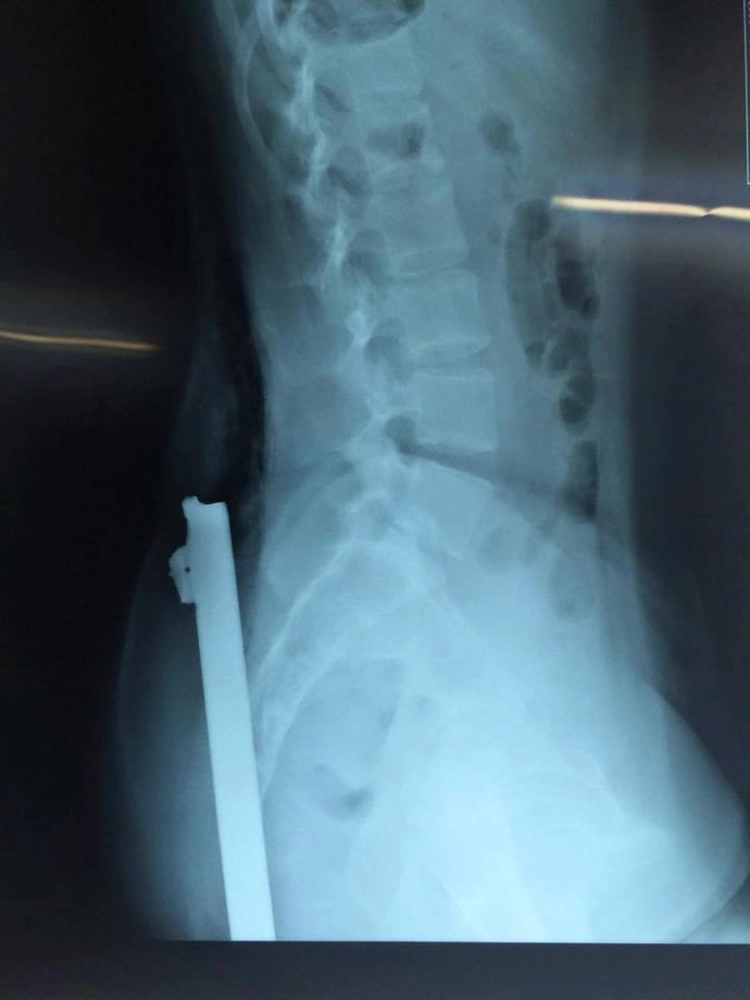

Kết quả chụp X-quang cho thấy, thanh sắt dài khoảng 40cm đâm từ phía sau, dưới mông xuyên đến tận thắt lưng. Ngay sau đó, bệnh nhân nhanh chóng được mổ cấp cứu.